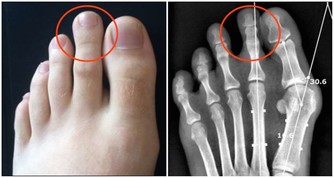

牙菌斑在剛剛形成的時候,人可以通過刷牙把它清除乾淨,但如果沒有及時清除乾淨,那麼牙菌斑就會發展變為牙結石,最為糟糕的是牙結石粗糙的表面更容易吸附牙菌斑,這就形成惡性循環,從而加重牙齦的炎症和出血。